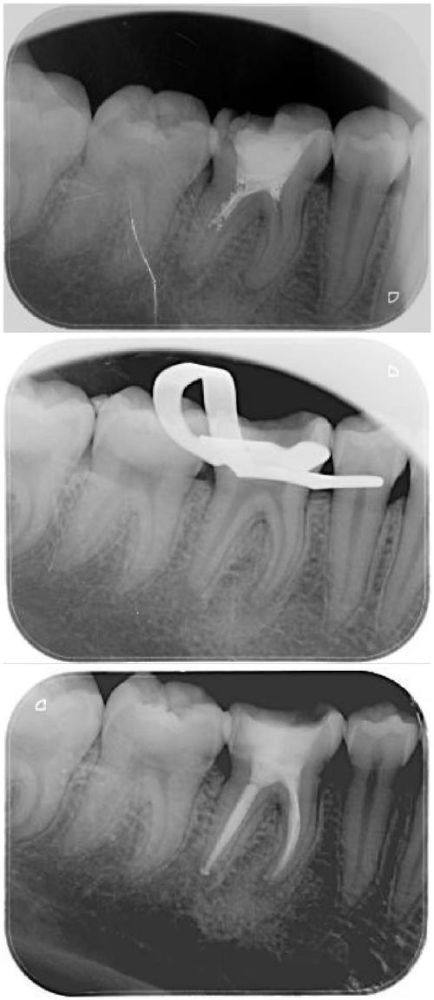

根管治疗:具备解决牙髓等口腔疑难问题的能力,操作专精规范,能缓解牙齿疼痛等不适症状。